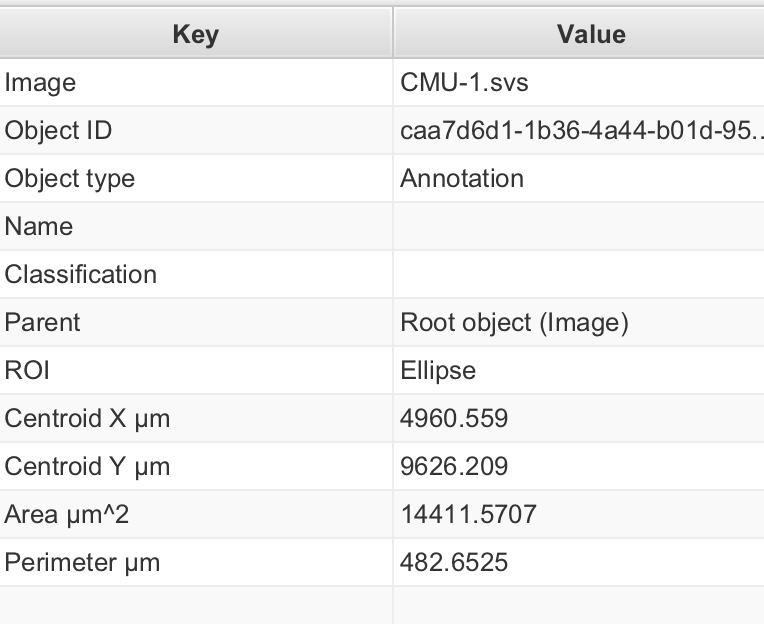

1-3:查看图像属性

通常,QuPath 窗口左侧有一个面板:分析面板。如果没有,请单击工具栏上的分析面板按钮将其打开。

这里有几个选项卡,您稍后会遇到。现在,单击**“图像”**选项卡以获取与您的图像相关的属性表。

2-7:查看测量结果

仍在分析面板中,在注释列表下方,您应该看到一个表格,显示当前选中对象的测量结果。如果您点击另一个注释,此表格应会自动更新。